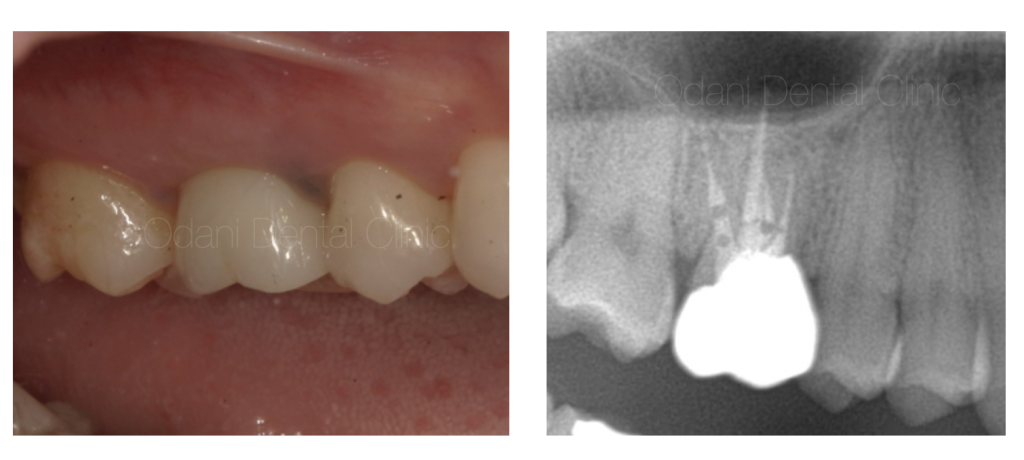

診察および画像検査の結果、歯の周囲に黒い影(赤丸)が確認できました。

このまま放置すると感染の範囲が拡大し、上顎洞炎を併発する可能性も考えられました。

CT画像を頼りに、30倍まで拡大できる歯科用マイクロスコープ下で根管を探索していきました。

すると、隠れた4本目の根管(黄色の点線部)が発見されました。

根管治療後4ヶ月で画像診断を行ったところ、幸い治療が奏功し周囲の影が消失したため、歯を保存できると判断し、かぶせものを作製して治療を終了しました。